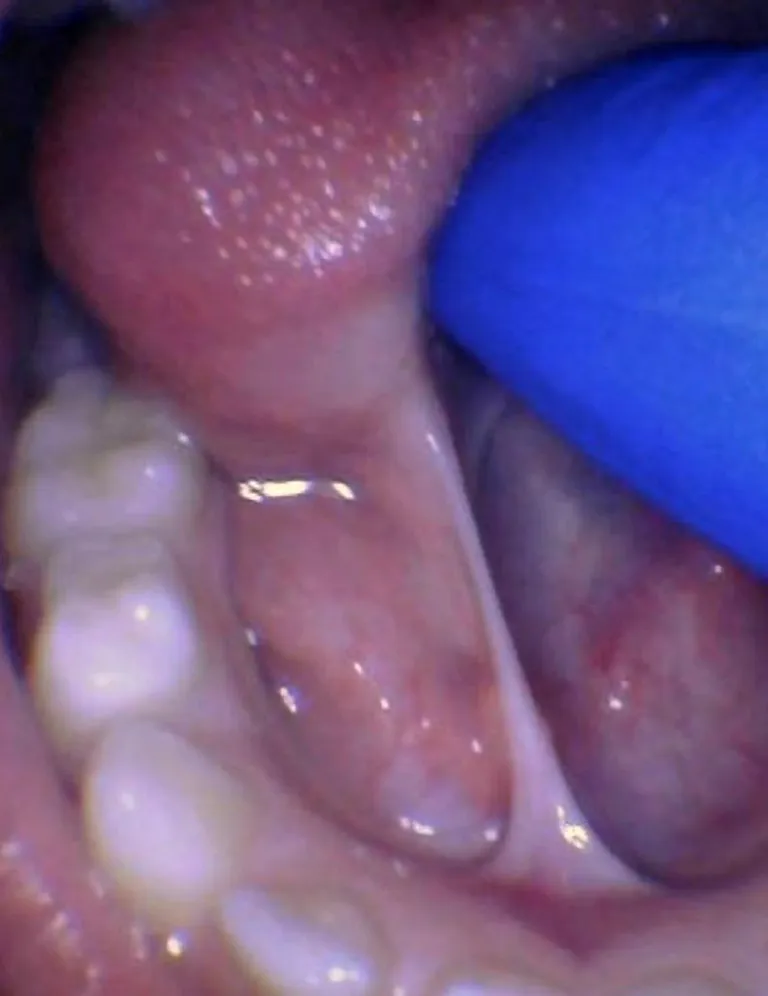

Le frein restrictif postérieur ou sous-muqueux a été décrit récemment par Genna-Watson et Coryllos (2004), le terme est donc encore peu connu par les professionnels de la santé. Chaque frein possède une composante sous-muqueuse, mais ce type de frein est totalement sous-muqueux. Il est palpable et visible avec manœuvre et peut restreindre la mobilité linguale autant qu'un frein restrictif antérieur. Certains considèrent qu'un frein postérieur correspond également au frein de type 3 selon Kotlow (distal par rapport à la pointe de la langue, terme qui semblerait être préférentiel selon Kotlow afin d'éviter toute confusion). D'autres considèrent que l'appellation est fausse, cependant, ce débat a lieu d'être en Amérique où l'on parle de "langue attachée postérieure", ce qui d'un point de vue anatomique porte à confusion, la partie postérieure de la langue étant la base de la langue. En France, il n'y aurait a priori aucune raison de penser que l'utilisation de ce terme est faux - cependant, de nombreux professionnels semblent encourager les praticiens à parler de mobilité antérieure (TRMR-TIP) ou postérieure (TRMR-LPS) impactée par un frein restrictif (ou autre, cf partie Diagnostic), et non de "posterior tongue-tie" ou "anterior tongue-tie".

En revanche, concernant la notion de "bande sous-muqueuse" de la ligne médiane, celle-ci n'est pas étayée par les dissections dans l'étude de Mills et al. de 2019 ; il a été démontré qu'il s'agirait d'un "pli médian défini" qui "peut être visible lorsque la langue est élevée, mais si une tension suffisante est exercée sur le fascia, il peut être palpé comme un tissu non distendu". Ils concluent alors que "le rôle de la chirurgie dans la division du fascia du plancher buccal dans ce sous-groupe et l'impact de l'intervention chirurgicale sur la biomécanique de la langue chez ces individus ne sont pas connus et justifient des recherches supplémentaires".

Ainsi, cela conclut qu'on ne peut rien conclure en l'état des données actuelles (et non que ça n'existe pas).